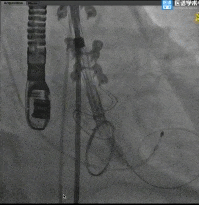

TaurusElite®首次释放

TaurusElite®首次回收

TaurusElite®二次释放

TaurusElite®二次回收